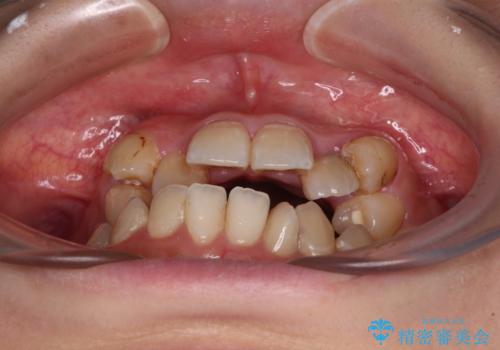

- 上下の歯が非接触であり、八重歯やむし歯を気にして来院された患者様です。

下顎骨の左右偏位はあるものの、上顎骨幅が相対的に狭い状態であったので、奥歯の咬み合わせが非常に乱れていました。

急速拡大装置により上顎骨幅を側方に拡大し、それを利用して八重歯を歯列に納めることにしました。

矯正治療後は全顎的にむし歯が多いため、セラミッククラウンやインレーにより補綴治療を行うこととしました。